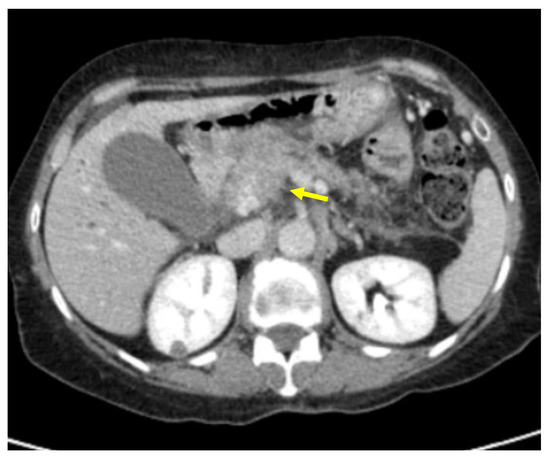

Tumor margins showed a significant difference in the two groups, appearing well-defined in only 6 (6.98%) metastatic patients and ill-defined in the remaining 80 (93.02%); in the non-metastatic group, the margins appeared well-defined in 132 (65.35%) and ill-defined in 70 (34.65%) tumors (Figure 2, Figure 3, Figure 4 and Figure 5).

Figure 3. Pancreatic lesion with well-defined margins (arrow) on CT examination in portal-venous contrast phase.